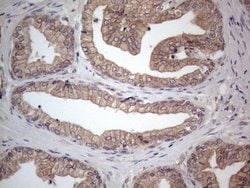

MTF1 Monoclonal Antibody for Western Blot, IHC (P)

| Immunohistochemistry (Paraffin), Western Blot | |